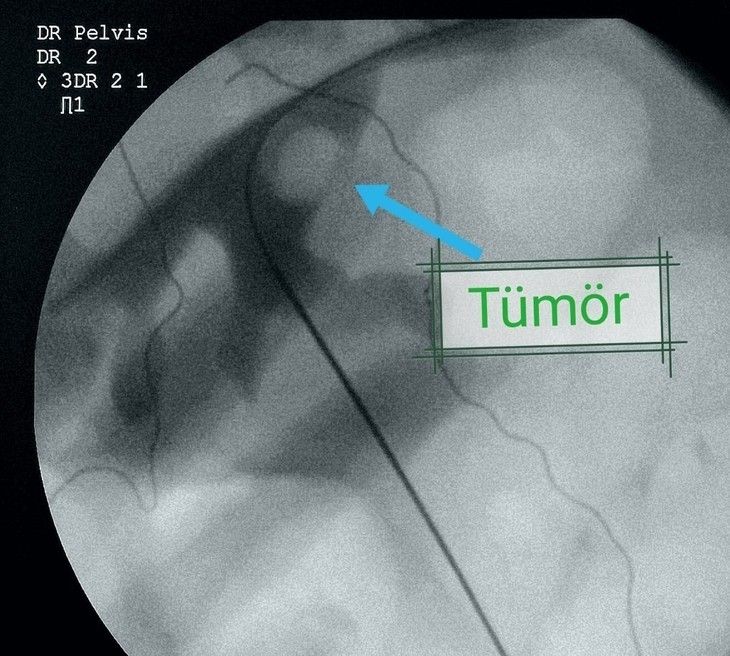

Yapılan tetkikler sonucunda hastanın nadir uygulanan yöntemle sağlığına kavuştuğunu ifade eden Op. Dr. Serhat Yentür, "Hastamıza kontrastsız emar (MR) çektik. MR’de sol böbreğin ana çıkış alanında 3 santimetrelik bir lezyon görüldü. Yani böbrek içinde bir tümör vardı ve onun temizlenmesi lazımdı.

Hastamıza bir şans tanıdık ve dünyada çok nadir yapılan bir yöntemi uygulamaya karar verdik. Bu yöntem böbreğe yandan girilerek orada bir tüp oluşturup böbreğin içine perkütan yöntemi ile girilmesinin ardından tümörü tur aletleriyle kazıma işlemiydi. Bu yöntem ve teknikle ameliyat yaptık ve çok başarılı oldu.